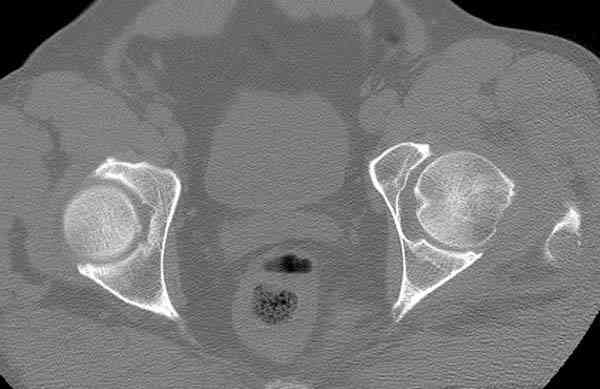

Здесь представлены снимки больного 65 лет, поступившего с диагнозом перелом

бедра после автоаварии.

В первый же день произведено антеградное штифтованием DePuy Trochanteric Nail.

На второй день (7) обнаружен пропущенный перелом,

сделаны Компьютерная Томограмма

и проведены шурурпы через и спереди штифта без удаления.

Послеоперационные снимки